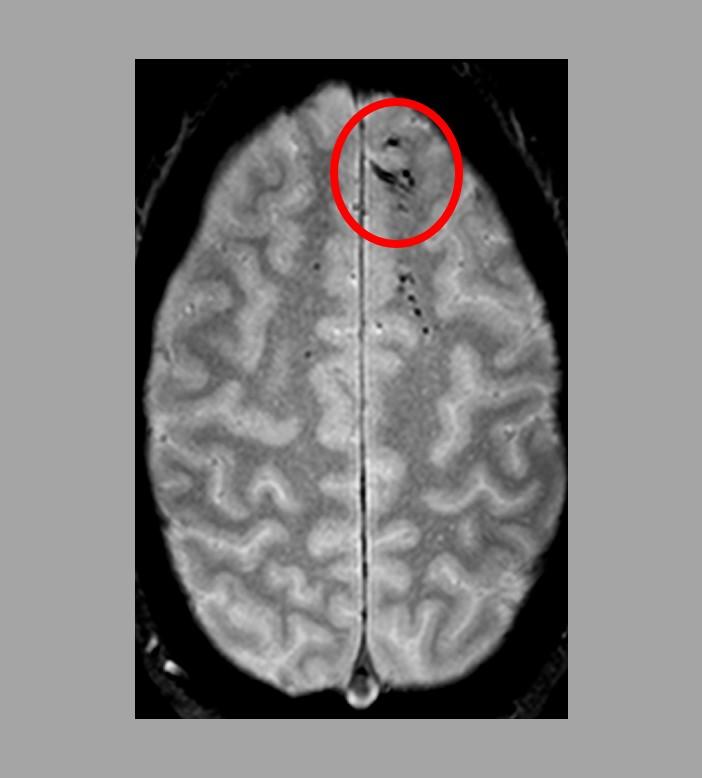

Using advanced imaging, researchers have uncovered new information regarding traumatic microbleeds, which appear as small, dark lesions on MRI scans after head injury but are typically too small to be detected on CT scans. The findings published in Brain suggest that traumatic microbleeds are a form of injury to brain blood vessels and may predict worse outcomes. The study was conducted in part by scientists at the National Institute of Neurological Disorders and Stroke (NINDS), part of the National Institutes of Health.

The results showed that 31% of all study participants had evidence of microbleeds on their brain scans. More than half (58%) of participants with severe head injury showed microbleeds as did 27% of mild cases. The microbleeds appeared as either linear streaks or dotted, also referred to as punctate, lesions. The majority of patients who exhibited microbleeds had both types. The findings also revealed that the frontal lobes were the brain region most likely to show microbleeds.